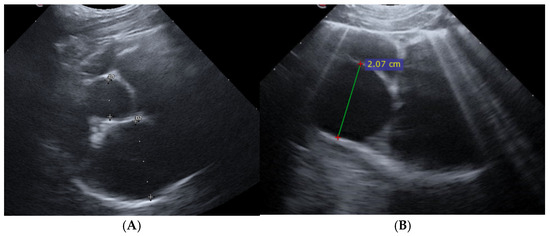

Upon presentation, cats were first stabilized in an oxygen cage (flow rate 3 L/min), resulting in an estimated inspired oxygen concentration of 40–50%. The cats were subsequently sedated using an intramuscular injection of butorphanol (Dolorex; Intervet International B.V., Boxmeer, The Netherlands) at a dose of 0.2 mg/kg, and in case of pleural effusion a thoracocentesis was performed using a 20 gauge over-the-needle catheter (Vasofix, B. Braun, Melsungen, Germany) or butterfly needle (Venofix, B. Braun, Melsungen, Germany) connected to a three-way stopcock and a 20 mL syringe. The stabilized cats were positioned either in sternal recumbency or in a standing position, and given supplemental oxygen through flow-by for the duration of the POCUS exam [22]. To minimize stress and expedite the process, cats were not shaved for the POCUS. Alcohol was applied to the fur to optimize imaging. Two-dimensional grey scale video cineloops were obtained and recorded from the right parasternal position in the standard long-axis 4-chamber and the short-axis view at the level of the heart base [22,23]. The examination and recording of cineloops was repeated three hours (T3) following parenteral furosemide (Dimazon; Intervet International B.V., Boxmeer, The Netherlands) administration by the same examiner. All left atrial measurements were reviewed from the recorded cineloops by an ECC resident, who was not present during the POCUS. Criteria for left atrium enlargement were set at a LA:Ao ratio exceeding 1.8 and a LAD greater than 18 mm (Figure 1A) [24,25,26]. Both criteria (LA:Ao ≥ 1.8 and LAD ≥ 18 mm) had to be present for inclusion; cats not meeting both criteria were excluded. Video cineloops were recorded at maximal left atrial size, and from these recordings three separate measurements were obtained; the average of these three measurements was used for data analysis.

Figure 1. Two-dimensional Point-of- Care Ultrasound images showing the measurement of left atrium in right parasternal views at admission. (A) Measuring left atrium D2 and aorta D1 at a short axis view at maximum left atrial size to determine left atrial to aortic ratio (LA:Ao). In this example, the LA:Ao ratio measured 2.17. (B) Measurement of left atrial dimension (20.7 mm) on a right parasternal long axis 4-chamber image. Several pulmonary B-lines can also been appreciated.